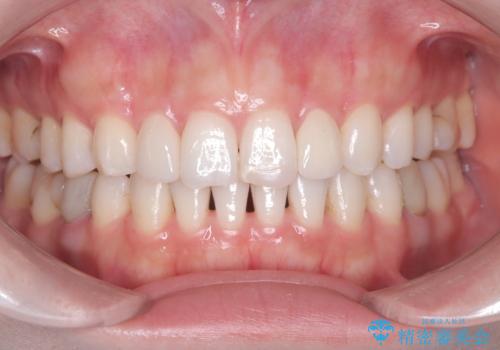

矯正によって歯並びはきれいに整いましたが、前歯全体のバランスをより自然で美しく仕上げるため、上顎左右2番にオールセラミッククラウンによる審美修復を行いました。

矮小歯はもともと歯が小さいため、削る量を最小限に抑えた負担の少ない治療が可能です。

また、自然な色合いや形になるよう、歯科技工士と連携し、写真を撮影しながら細かく色合わせを行い、周囲の歯になじむよう丁寧に仕上げています。